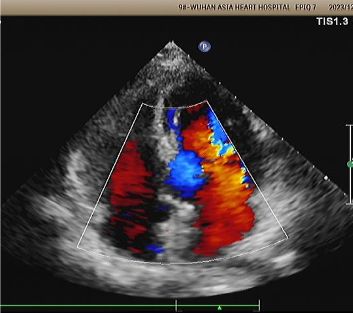

1-jähriges Echo:

No visible disc structures – replaced by 8mm tissue thickening at the septal implant site.

Zero residual shunt (rest or post-Valsalva).

Komplette Absorption des Geräts bestätigt.